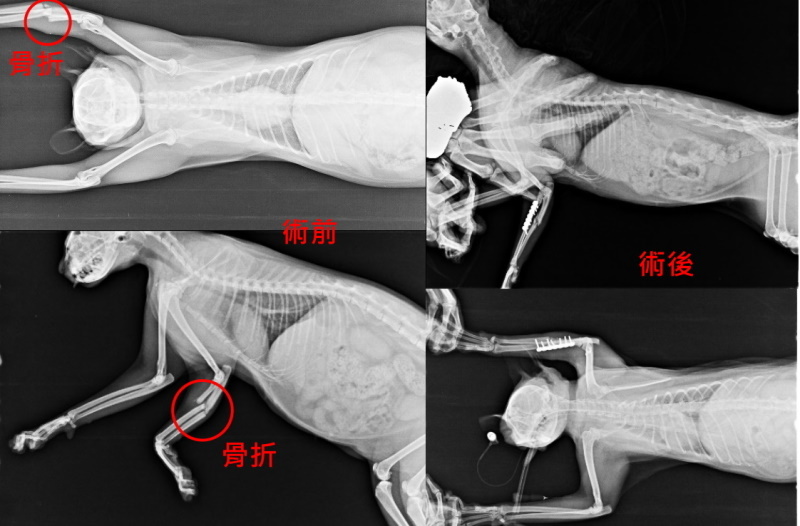

小山結紮後先帶回安養之家休養,等待復部的毛長出才擇日與大山放回烏來溫泉旅館由老闆繼續餵養,期間照顧員發現小山的腳無法著地,似有疼痛感,送醫X光檢查,發現小山的腳居然是斷的,原來一切都是上天的安排,一次救援的兩隻傷貓啊~~大山因傷口血淋淋遊客容易發現通報,但小山腳骨折一般人不易觀察,若非此巧合,小山的腳可能因為沒有醫療就此失去功能...

住院期間小山會主動攻擊、試圖要衝出籠外,除了手術固定外還進行骨折包紮避免任何傷害發生,狀況穩定後,已先帶回安養之家照顧,醫療費用還請各位幫忙。